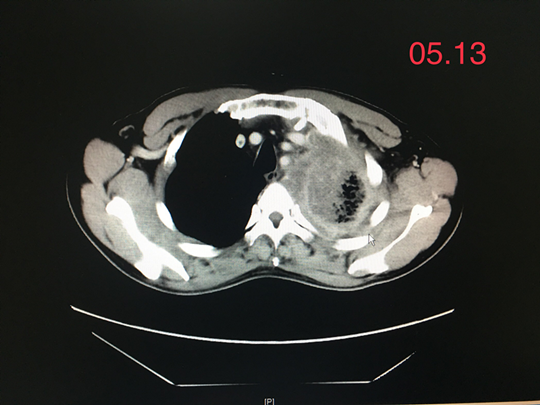

在进行胸腹部CT、肿瘤标志物等检查中,发现王先生左上肺有巨大占位,合并左侧大量胸腔积液,导致左肺明显的压缩、完全看不到肺叶,放疗科为其做了肺穿刺检查,最终确诊左肺腺癌。

就这样过了两个月,王先生再次复查胸部CT,发现其左肺肿瘤病灶基本消失了,治疗效果非常好!